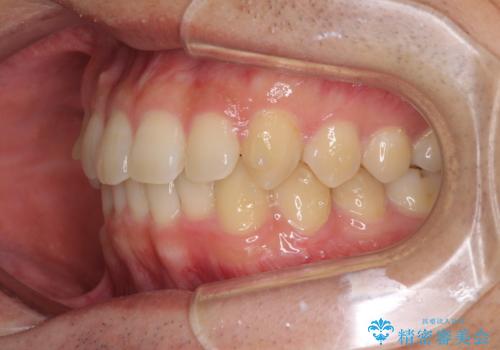

- 上下前歯のデコボコと深い咬み合わせを気にして来院された患者様です。

インビザラインによる上下歯列の拡大と、IPR(歯と歯の間を削る)にるスペースの獲得により、前歯のデコボコとディープバイトを改善することとしました。

もう少し下の前歯を整えたかったのですが、患者様の治療を早く終了させたいという希望により、細かい叢生を残しての終了となりました。